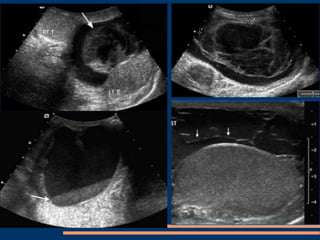

ORQUIEPIDIDIMI

TIS

CR

Absceso, imágenes pequeñas

hipoecogénicas intratesticulares.

Hidrocele reactivo.

Mismo paciente, Doppler periférico

Absceso, imágenes pequeñas hipoecogénicasintratesticulares. Hidrocele reactivo. Mismo paciente, Doppler periférico